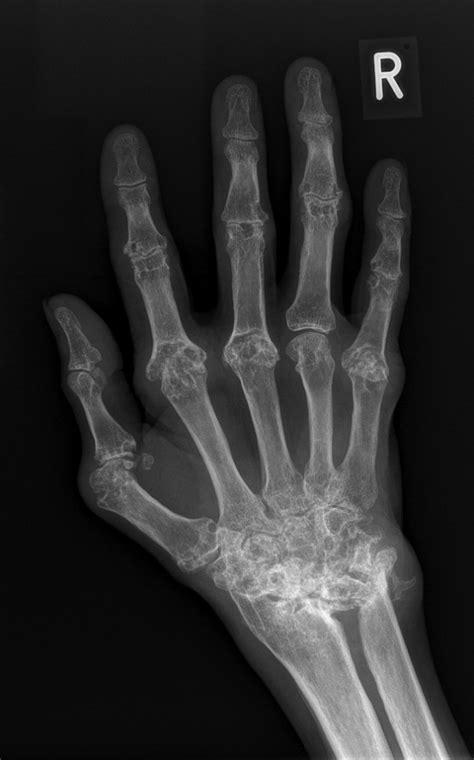

Rheumatoid Arthritis – Hand - Radiology At St. Vincent's University

Rheumatoid arthritis – hand - Radiology at St. Vincent's University www.svuhradiology.ie

arthritis rheumatoid hand ankylosing spondylitis radiology dagger sign svuhradiology ie

Rheumatoid Arthritis - Hands - Radiology At St. Vincent's University

Rheumatoid arthritis - hands - Radiology at St. Vincent's University www.svuhradiology.ie

arthritis rheumatoid hands radiology case study studies pain